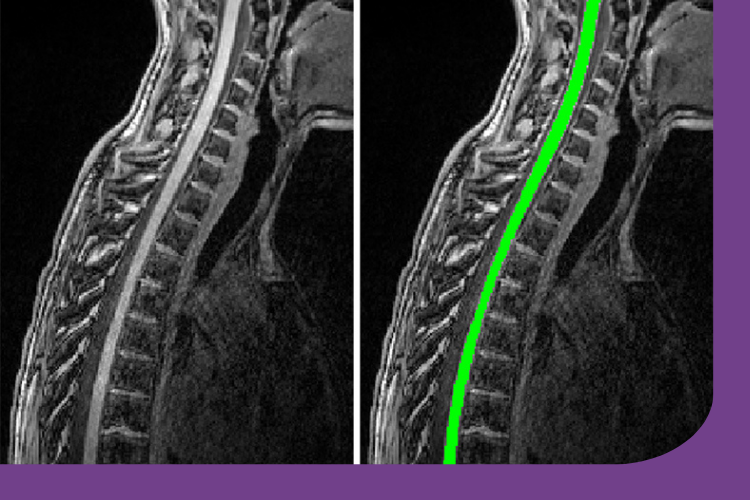

New funding for spinal cord imaging research study

Jan 2025: Congratulations to Dr Rozanna Meijboom and colleagues from the MS imaging group, who have recently been awarded funding for a research study to examine changes in the spinal cord of people with multiple sclerosis (MS).